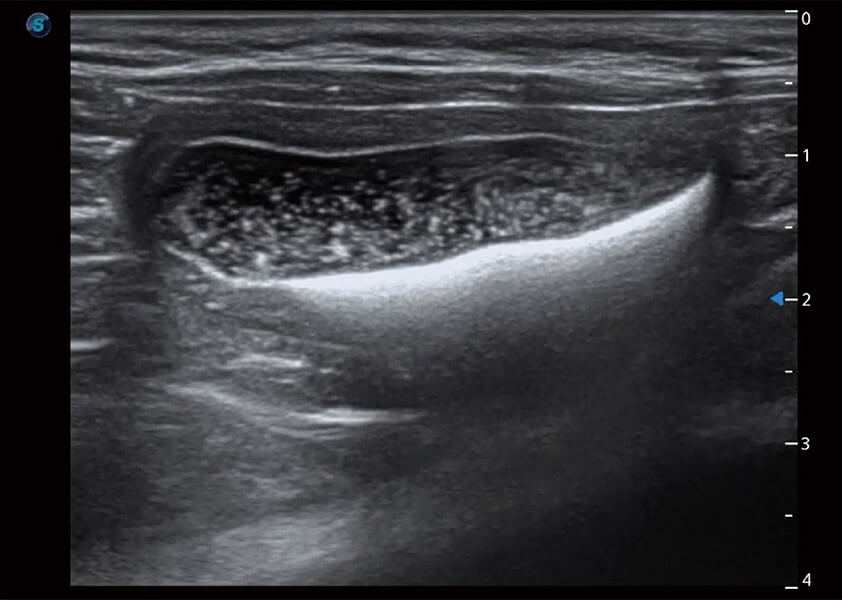

(犬)膽囊泥沙

(貓)膀胱結(jié)晶